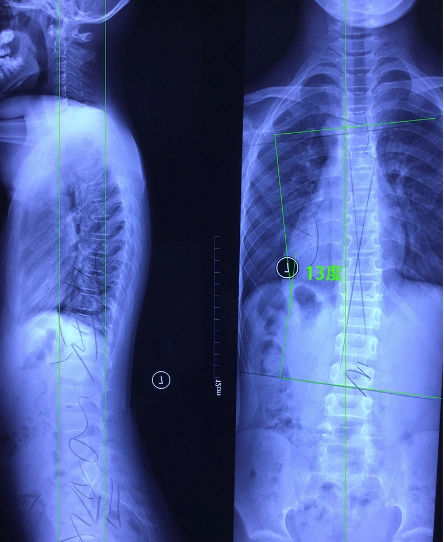

脊柱侧弯矫正3个月剃刀背14度减至0度73